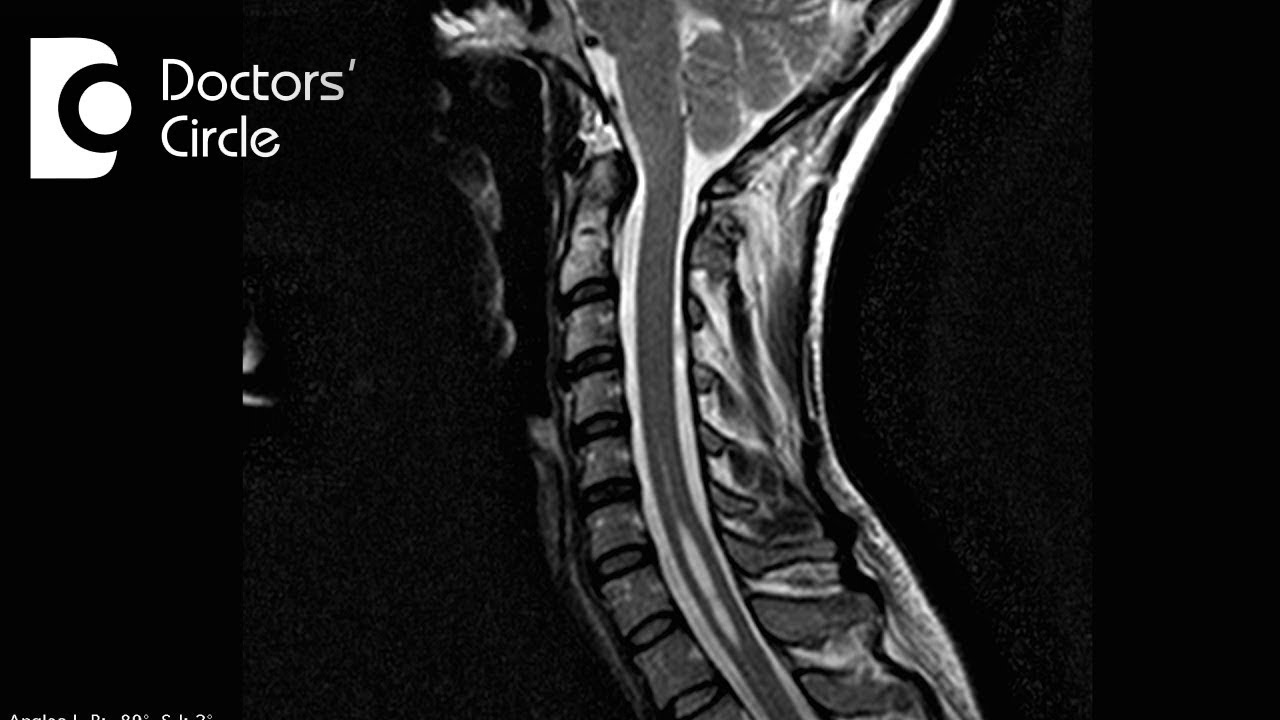

Symptoms of Syringomyelia - Dr. Vykunta Raju K N

Syrongomyelia is one type of spinal dysraphism. The manifestation of syringomyelia depends upon which part of the spinal cord is involved. Usually if it is involved in the cervical cord, in the upper part of the spinal cord there will be weakness of the upper limb or involvement of ulcers. There is loss of pain and touch sensation over the fingers and hands where they will sometimes cause burns and non healing ulcers. If it is not treated it can cause involvement of bone with osteomyelitis. They will be having difficulty during work. If it is involvement of the lower part of the spinal cord there will be manifestations similar to the upper limbs in the lower limbs where non healing ulcers, weakness. If it is severe they will be having bowel and bladder involvement. The patient may not feel any pain due to non healing ulcers. You need to treat it appropriately.